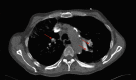

An Audaciously Aneurysmal Atrium